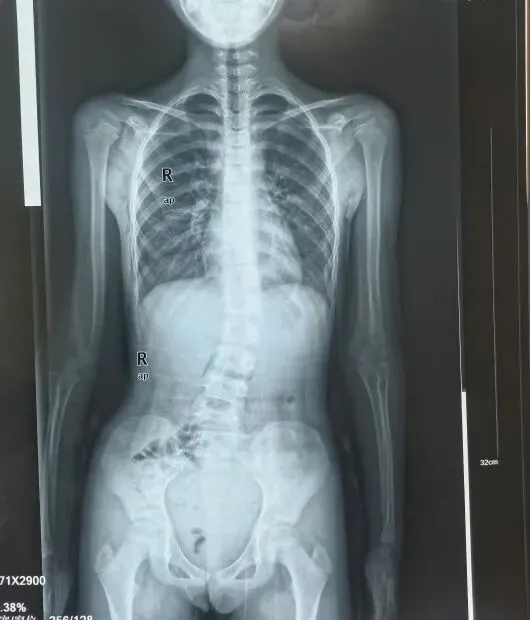

既往训练效果

治疗前

治疗后